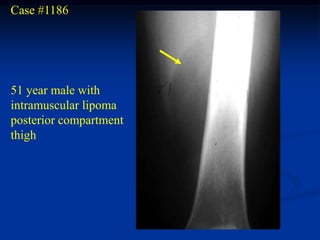

Case #1186

51 year male with

intramuscular lipoma

posterior compartment

thigh

Case #1186 51 yearmale with intramuscular lipoma posterior compartment thigh

• 58.

• 59.